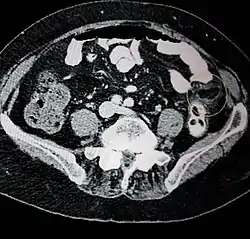

| Epiploic appendagitis seen on CT scan. | |

Ultrasound and CT scans are the normal means of positive diagnosis of epiploic appendagitis. Ultrasound scans show "an oval, non-compressible hyperechoic mass with a subtle hypoechoic rim directly under the site of maximum tenderness".[5] Normally, epiploic appendages cannot be seen on CT scan.[5] After cross-sectional imaging and the increased use of abdominal CT for evaluating lower abdominal pain, EA is increasingly diagnosed. Pathognomonic CT scan data represent EA as 2–4 cm, oval shaped, fat density lesions, surrounded by inflammation. Contrasting with diverticulitis findings, the colonic wall is mostly unchanged.